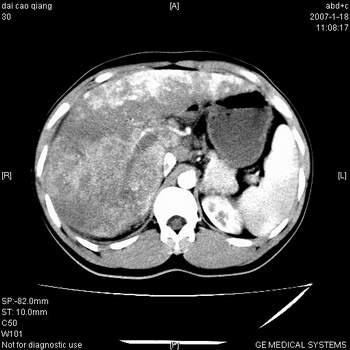

符合巨块型肝癌表现:

1、平扫低密度,增强后表现为快进快出。

2、动脉期可见迂曲的动脉供血血管

3、并可见门静脉右支癌栓形成

4、可见假包膜

5、腹主动脉旁结节影,考虑肿大淋巴结。

典型的肝右叶巨块型肝癌破裂、门脉瘤栓形成。

肝右叶巨大不均匀低密度肿块,前缘有假包膜,增强明显的呈快进快出表现,门脉右支有癌栓,病人虽然年轻但还是首先考虑肝右叶巨块形肝癌,病人血象高只能说有合并感染。不支持肝脓肿。

肝右叶巨块型肝癌破裂、门脉瘤栓形成。